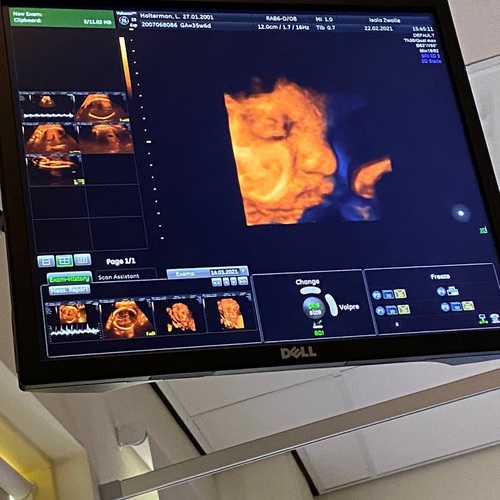

Wat een mooi beeld heb je !? Gewoon bij je gynaecoloog??

In het ziekenhuis bij de polikliniek 馃グ